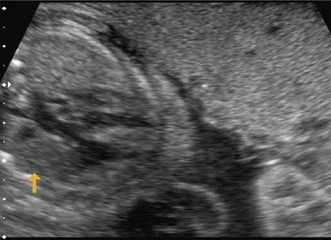

出生後の管理体制により大きく児の予後が左右される疾患に,重症の先天性心疾患がある。胎児心疾患の診断は,ある程度意識を持って診断に当たらねば異常に気が付かない。ここに,胎児の心疾患の診断を特別に考えねばならない理由がある。図7は,NTがあり,単一臍帯動脈,子宮内発育遅延があった。胎児心臓の精査では,大動脈の騎乗が見つかった。出生後の診断はファロー四徴症。

![]() 図7 大動脈騎乗,妊娠27週 染色体検査は正常核型。 ほかに単一臍帯動脈,子宮内発育遅延, 妊娠初期にNTがあった。 |